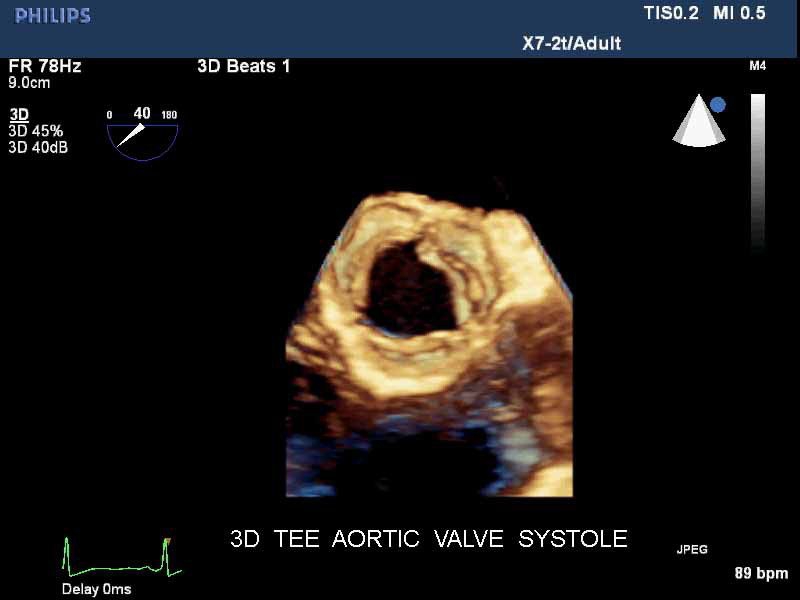

• Чреспищеводная эхокардиография

• Live 3D TEE: Эта функция позволяет проводить чреспищеводную эхокардиографию в режиме реального времени, что позволяет оценить механические сокращения сердца с точностью, необходимой для оценки результатов хирургического вмешательства.

• 3D эхо-кг в реальном времени (Live3DEcho): Эта технология позволяет получать объемные 3D изображения сердца в режиме реального времени.

• Чреспищеводный УЗИ датчик Philips Х7-2T